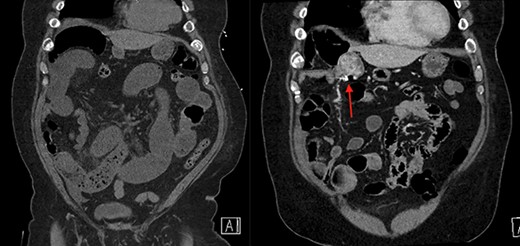

The patient is a 69-year-old male with a past medical history of hypertension, chronic kidney disease, chronic obstructive pulmonary disease, right renal cancer status post-laparoscopic nephrectomy in 2016 (pathology showed renal cell carcinoma with invasion into the adrenal gland, Fuhrman nuclear grade 3–4, pT4 pN0, Stage IV) who presented to the emergency room (ER) with abdominal pain. The patient recently underwent an esophagogastroduodenoscopy and a colonoscopy the week prior as a workup for anemia, which were unremarkable. Since then, he started having intermittent abdominal pain and bloating. The CT abdomen and pelvis without contrast in the ER showed multiple dilated small bowel loops with a transition point in the right lower quadrant (Figs 1 and 2). Due to his history of previous abdominal surgery, this was diagnosed as a small bowel obstruction secondary to adhesions. He was initially managed with a nasogastric tube and gastrografin study. On hospital Day 1, he had minimal output from his nasogastric tube and started to have bowel movements; therefore, his nasogastric tube was removed and he was started on a liquid diet. His diet was advanced, and on hospital Day 2, the patient was discharged.

On the left is the initial CT scan non-contrast demonstrating dilated small bowel loops and a transition point in the right lower quadrant. On the right is the CT angiography (CTA), performed a week later, showing a mass and pill cam in the right upper quadrant.

The next week, unbeknownst to his Gastroenterologist about his recent small bowel obstruction admission, he then proceeded with a capsule endoscopy study to assess for other causes of his anemia. He tolerated the pre-operative bowel preparation without issues. After swallowing the capsule, he subsequently had bloody bowel movements. He then went to the ER and found to have a hemoglobin of 7.1, which was decreased from his prior week’s hospitalization, 8.4. A CT angiography (CTA) abdomen and pelvis was then performed that showed a 4 × 6 × 4.1 cm mass in the right upper quadrant with the capsule endoscopy at the level of the mass (Figs 1 and 2). The images from the capsule were unremarkable. On review of his imaging with radiology, it appeared that this mass was not apparent without IV contrast on his previous CT scan a week prior. In addition, a prior CT abdomen pelvis with IV contrast 10 months ago was negative for a small bowel mass. A repeat abdominal and pelvis CT with oral and IV contrast was done for confirmation. This re-demonstrated the 6 cm mass with the capsule stuck proximal to it; therefore, we performed a diagnostic laparoscopy.